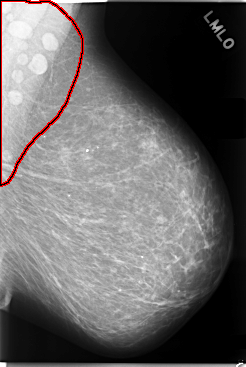

C_0083_1.LEFT_MLO

LEFT_MLO LINES 5864 PIXELS_PER_LINE 3936 BITS_PER_PIXEL 12 RESOLUTION 50 OVERLAY

FILE: C_0083_1.LEFT_MLO.OVERLAY

TOTAL_ABNORMALITIES 1

ABNORMALITY 1

LESION_TYPE MASS SHAPE OVAL MARGINS CIRCUMSCRIBED

ASSESSMENT 5

SUBTLETY 5

PATHOLOGY MALIGNANT

TOTAL_OUTLINES 1

BOUNDARY